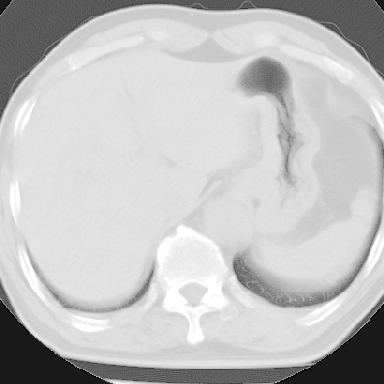

标题: CT8275:M 77 反复咳嗽咳痰10多年,慢性支气管炎请分析 [打印本页]

标题: CT8275:M 77 反复咳嗽咳痰10多年,慢性支气管炎请分析

m 77 反复咳嗽咳痰10多年,再发加重4天

两肺未见明显异常;主动脉弓硬化;左侧冠状动脉硬化?

这份病例诊断慢支并气肿可能属过诊,首先慢支的临床诊断标准是严格的,应该弄清楚,其次ct表现是否符合该病表现,本例老年人ct肺窗表现应属正常,不要跟着临床跑。